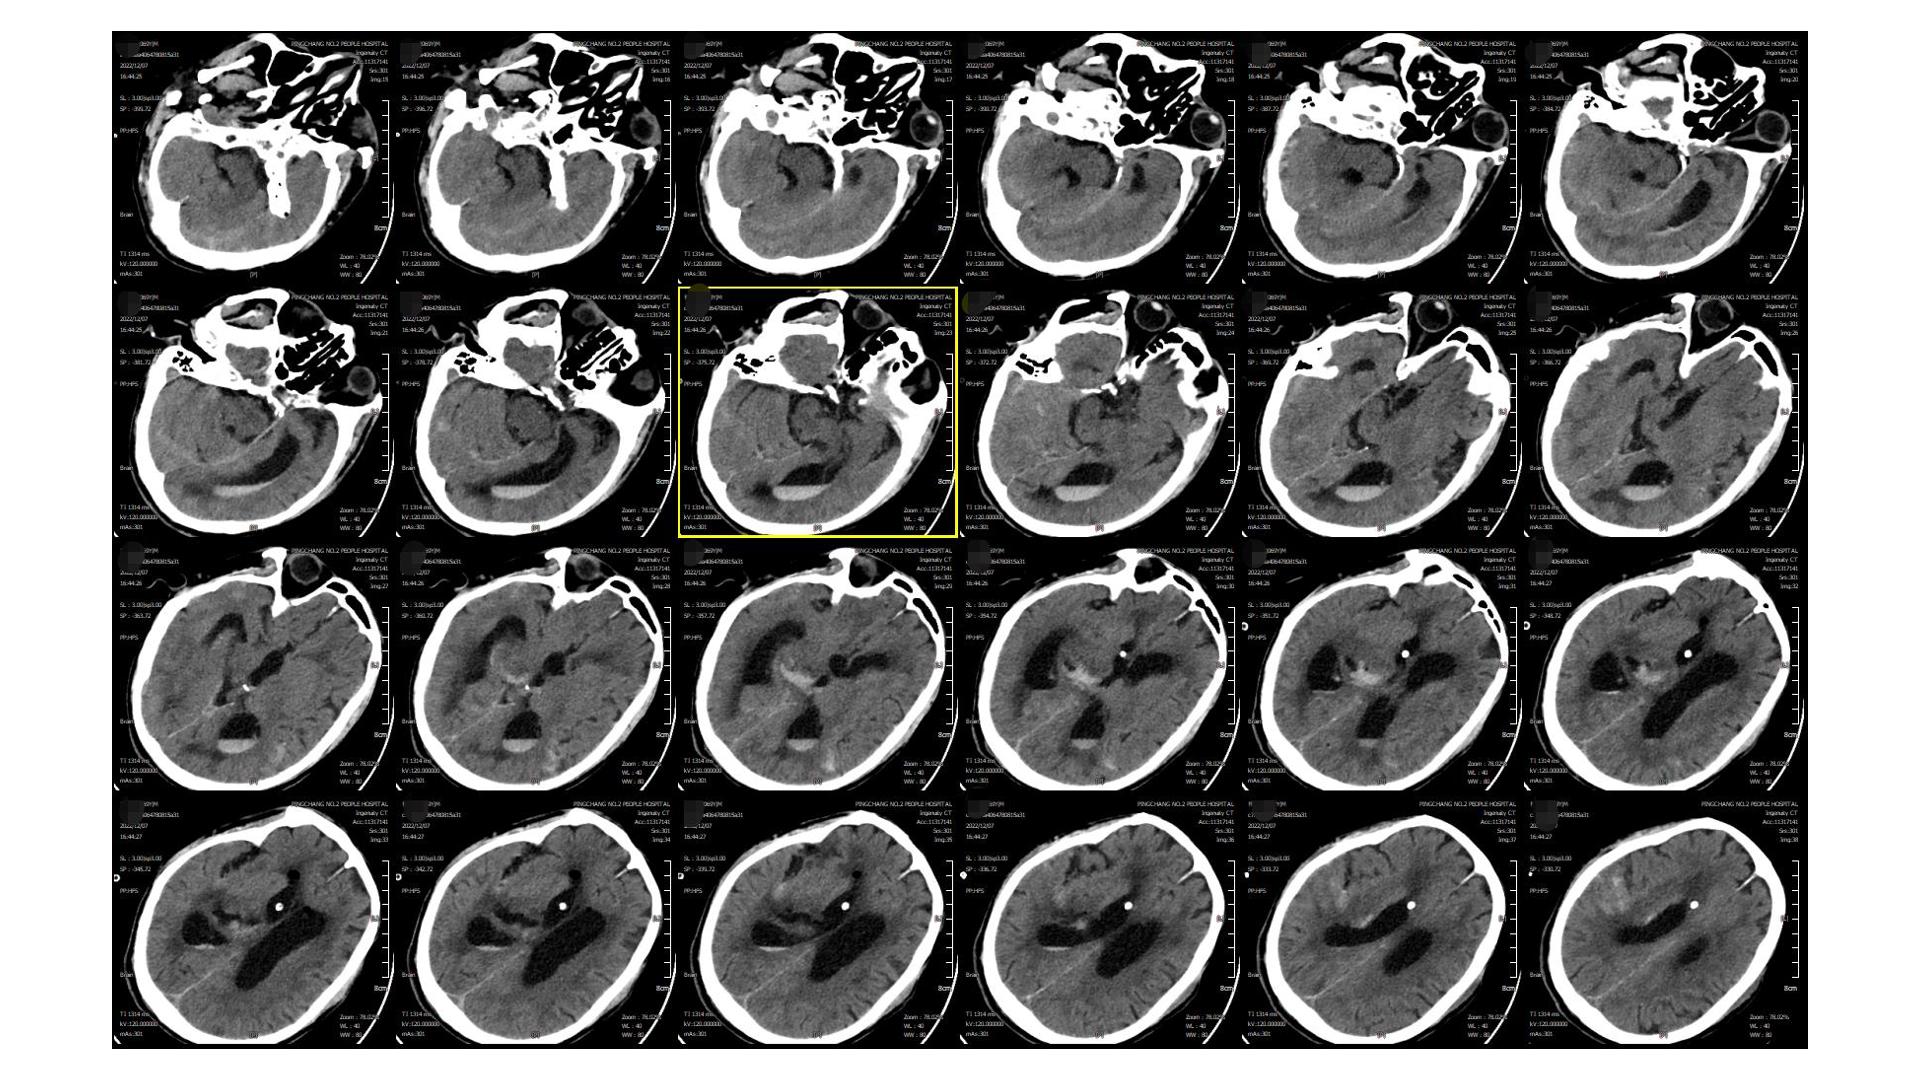

2022.12.03